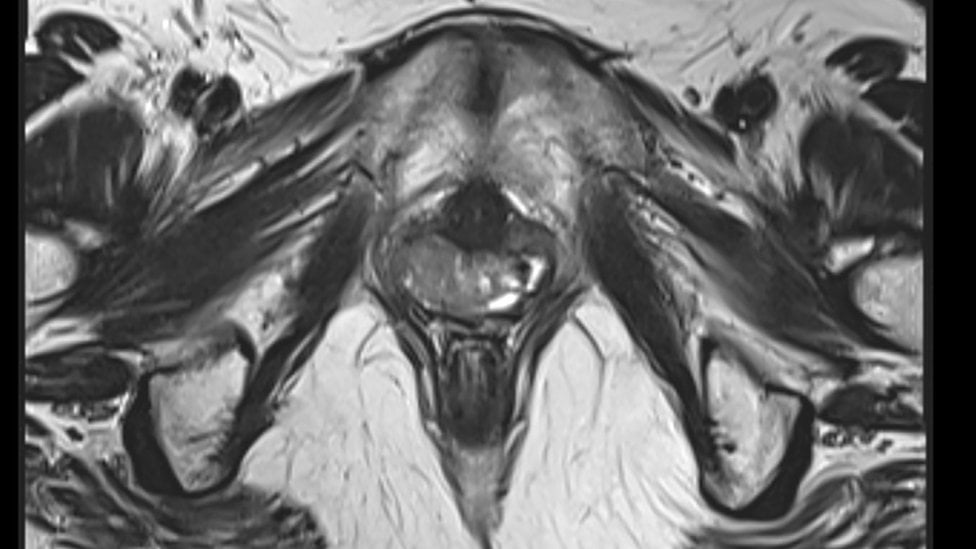

"Podemos pedir un examen pélvico, una ecografía y también una prueba genética para verificar si la paciente tiene los cromosomas XX", explica Claudia Takano, coordinadora del ambulatorio de malformaciones genitales de la Universidad Federal de São Paulo (Unifesp), el único que trata el síndrome por el Sistema Único de Salud, público y gratuito en Brasil.

Es una malformación congénita que provoca la ausencia del útero o un desarrollo incompleto de una porción de la vagina.

Esta condición surge durante la embriogénesis, es decir, poco después de la formación del embrión, en la sexta semana de gestación.

"El síndrome es como una alteración anatómica. Modifica la forma del órgano, pero la mujer tiene ovarios y se desarrollan sus características sexuales. Las niñas suelen acudir al médico porque no menstrúan", explica Natália Piovani, ginecóloga y profesora de la Universidade Positivo, en Curitiba (Brasil).